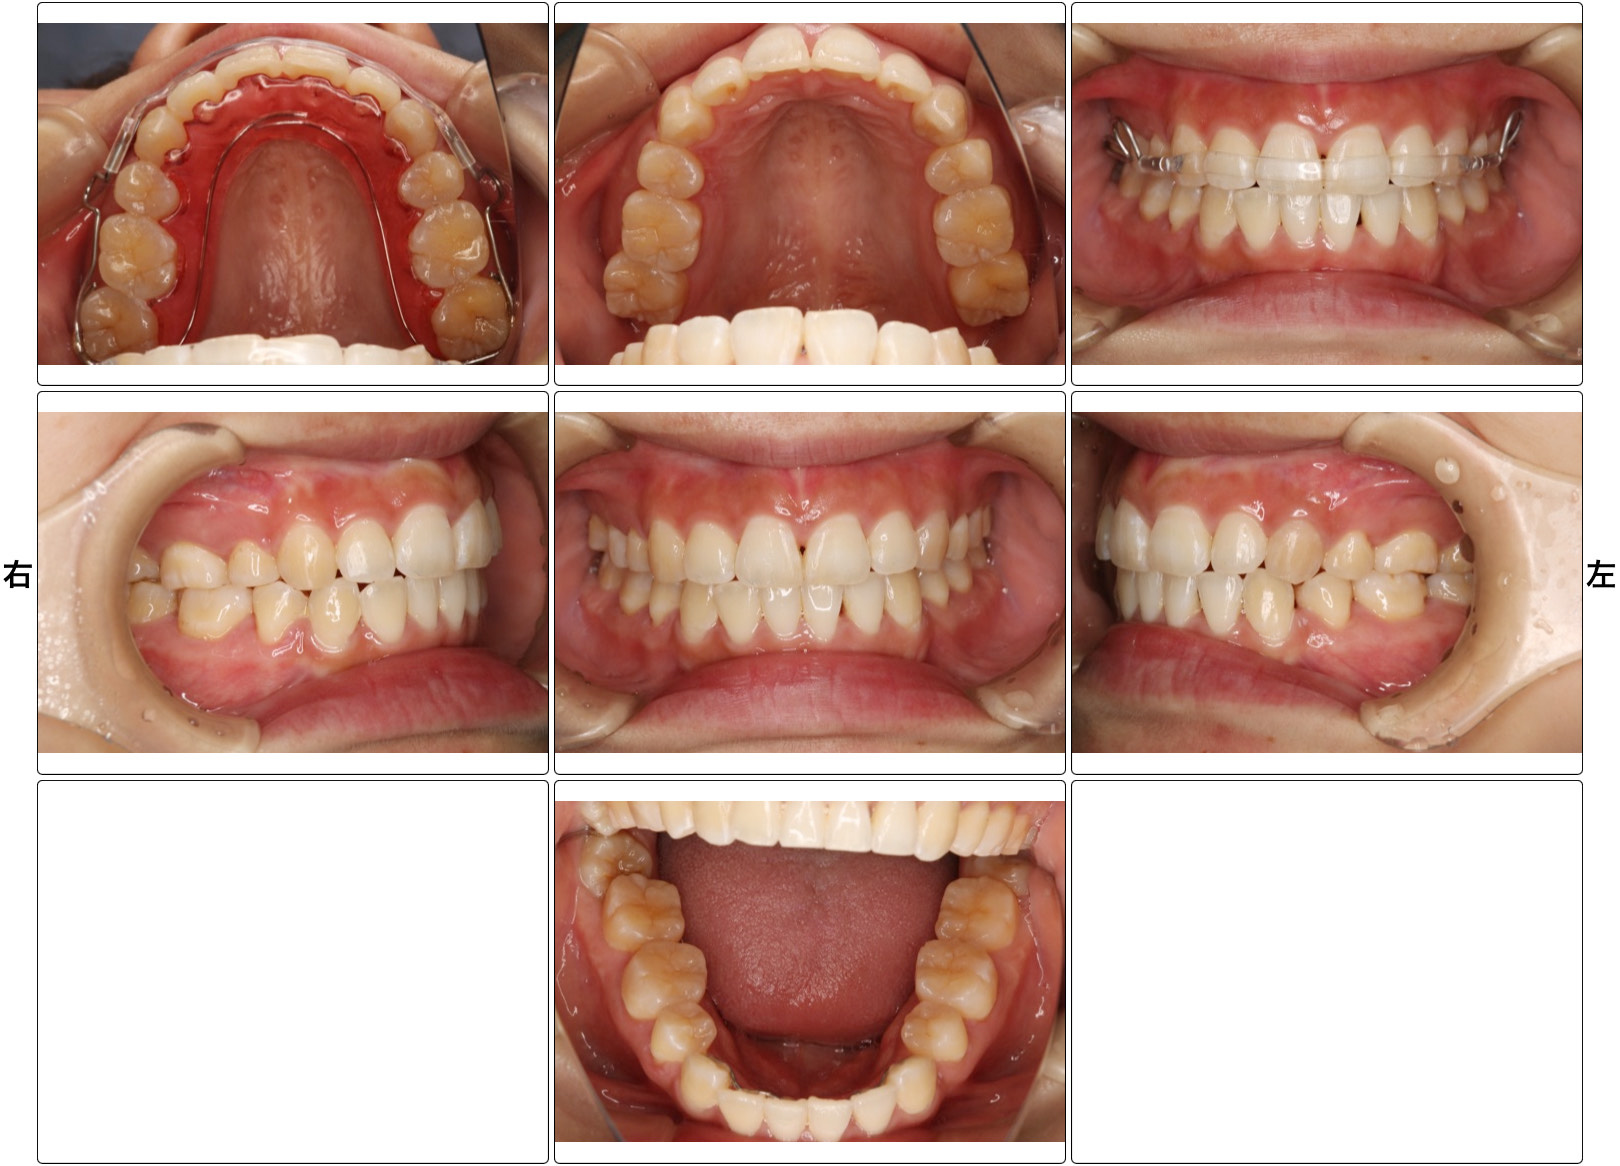

矯正治療の症例

- 治療の説明

- ブラケット矯正を行いました。

上下顎前突、叢生、オープンバイトの患者様です。上下左右4番目の歯を抜歯し、マルチブラケットを使用して歯並びを治しました。 - リスク

- 痛みを伴う可能性がある。口内炎が出来る可能性がある。歯根吸収の可能性がある。ブラックトライアングルができる可能性がある。

- 費用

- 85万(税込935,000円)〜、+調整料